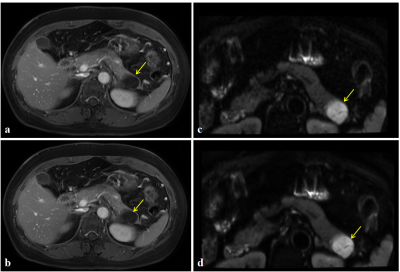

A typical set of DL reconstruction and conventional reconstruction images are shown in Figure 1.The subjective evaluation results of DL Recon 2D Ax FSE T1WI +C and DL Recon Ax FOCUS DWI were significantly better than their original images (The results are shown in Figure 2 and Figure 3).

Fig.1 MR images comparison in a 49-years-old female patient with mucinous cystadenoma (yellow arrows). a: Image of 2D Ax FSE T1WI +C before built-in DL Recon. b: Image of 2D Ax FSE T1WI +C after built-in DL Recon. c: Image of Ax FOCUS DWI before built-in DL Recon. d: Image of Ax FOCUS DWI after built-in DL Recon. Compared with the original images, the images obtained after the built-in DL Recon has lower noise, clearer outline of the pancreas, and better display of the lesion area.